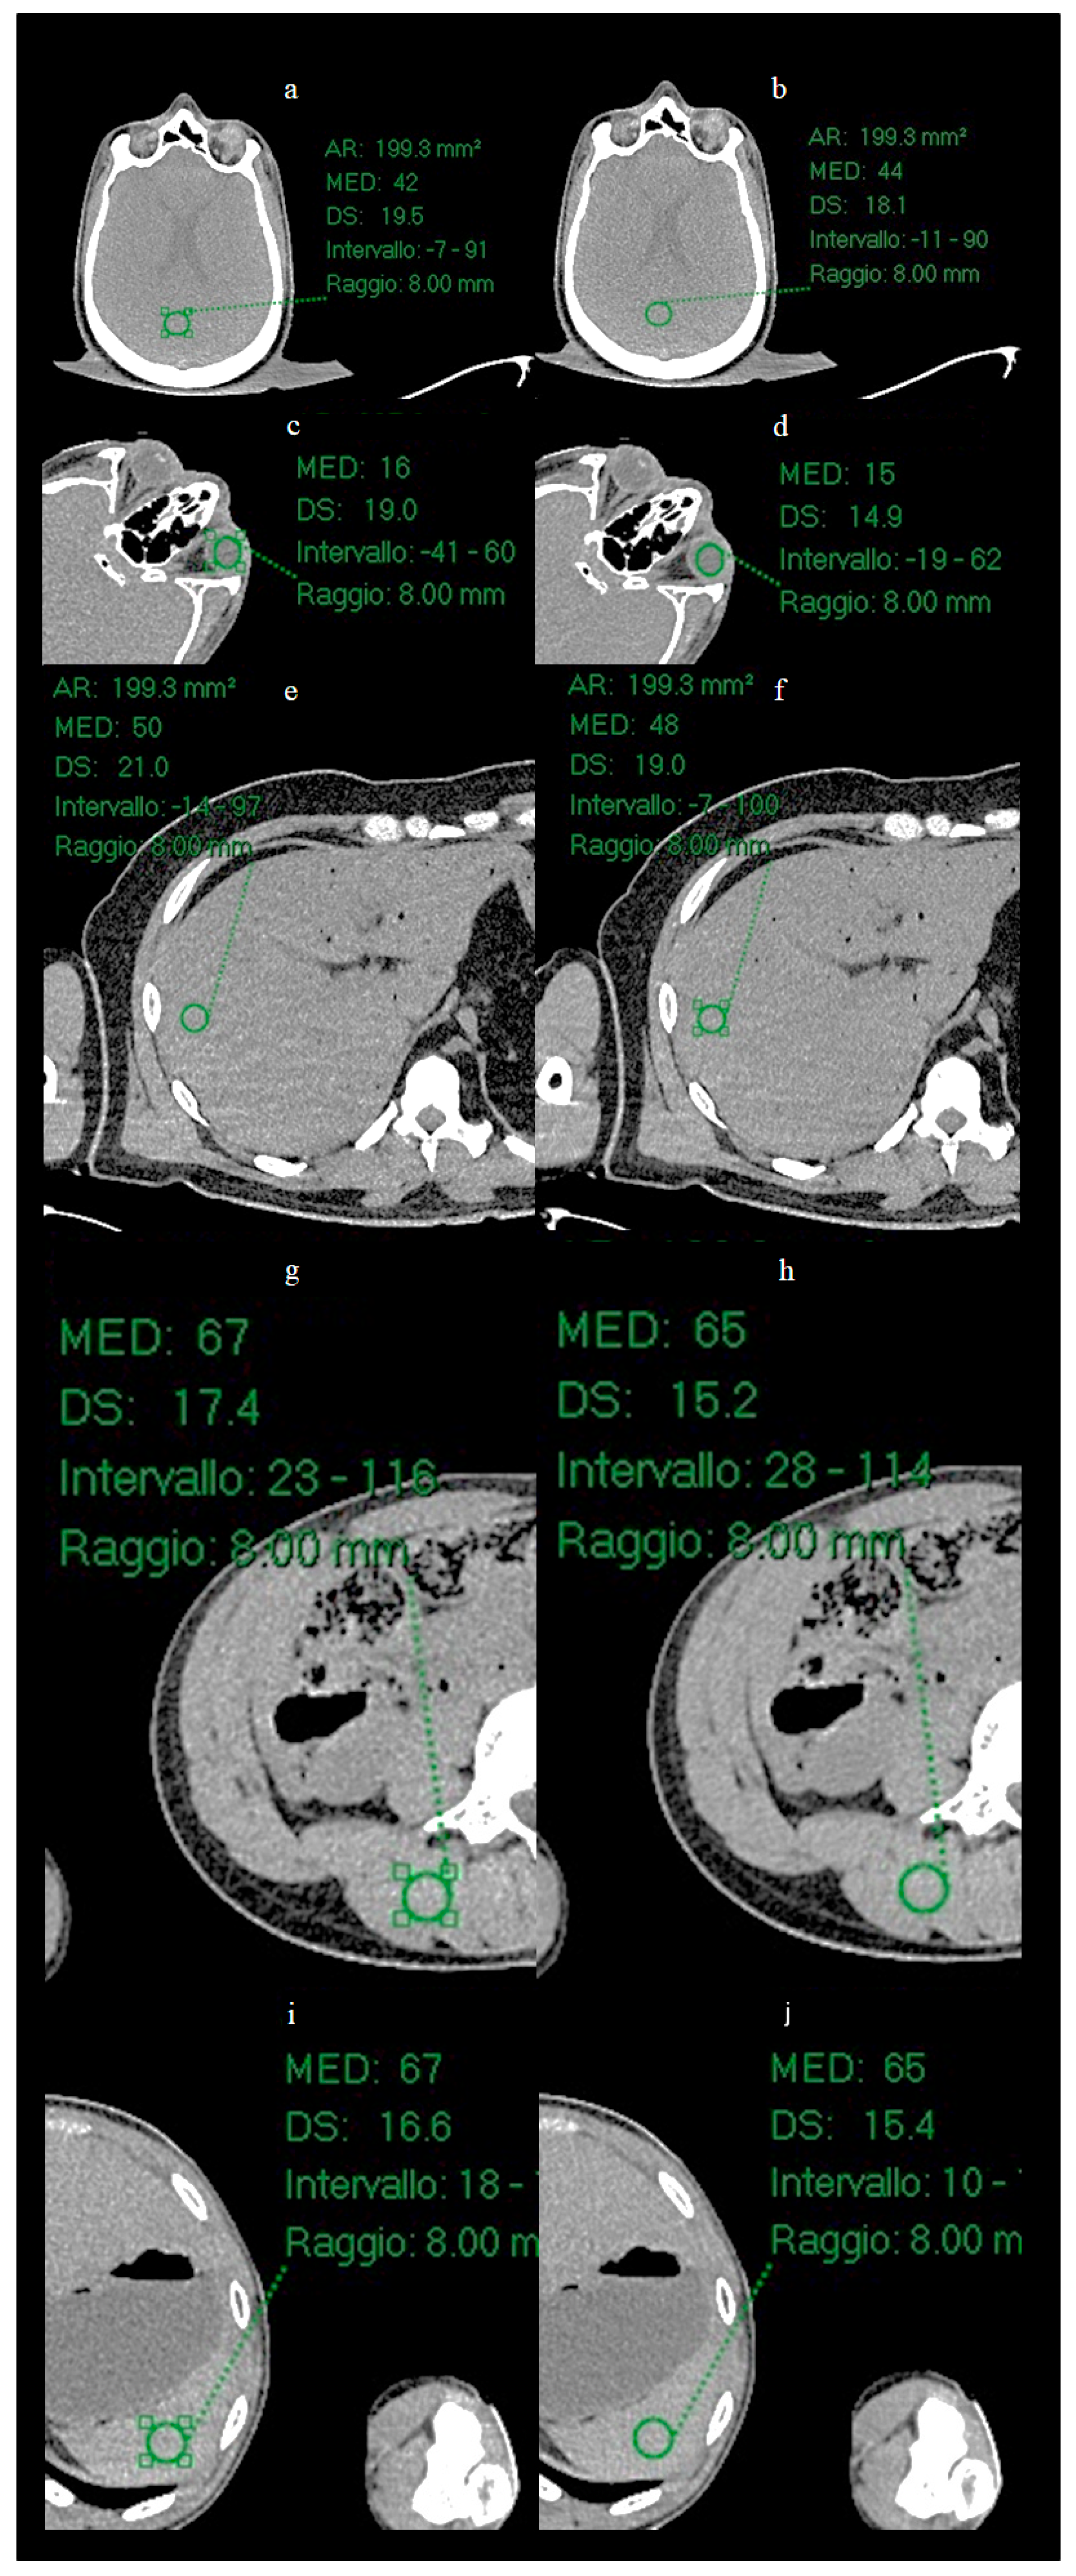

In the present study, a quantitative noise analysis was also performed by applying circular regions of interest (ROI) (radius 8 mm) at five anatomical locations (Figure 3): vitreous body, brain parenchyma, liver parenchyma, splenic parenchyma and paravertebral muscle. Within each ROI, the mean and standard deviation (SD) of the attenuation values (Hounsfield units) were calculated in order to characterize and compare the noise level before and after processing with ErisNet.

3.2. ROI Results

Circular ROI of radius 8 mm were placed on the images of the Test Set on the vitreous body (Figure 6), brain parenchyma, liver parenchyma, splenic parenchyma and paravertebral muscle, and the mean and SD of the mean values of Hounsfield Units (HU) were calculated for each ROI.

Figure 6.

Positioning of ROIs in five anatomical locations for quantitative analysis. Circular ROIs with a radius of 8 mm were placed on: (a,b) brain parenchyma, (c,d) vitreous body of the eye, (e,f) liver parenchyma, (g,h) lumbar paravertebral muscle, and (i,j) spleen parenchyma. For each anatomical location, the image on the left shows the low-dose acquisition, while the image on the right shows the corresponding result processed by ErisNet. These anatomical regions were selected to evaluate ErisNet’s performance on different tissue types and attenuation characteristics. The comparison demonstrates a consistent reduction in the standard deviation of Hounsfield units within the ROIs after processing with ErisNet (Table 4).